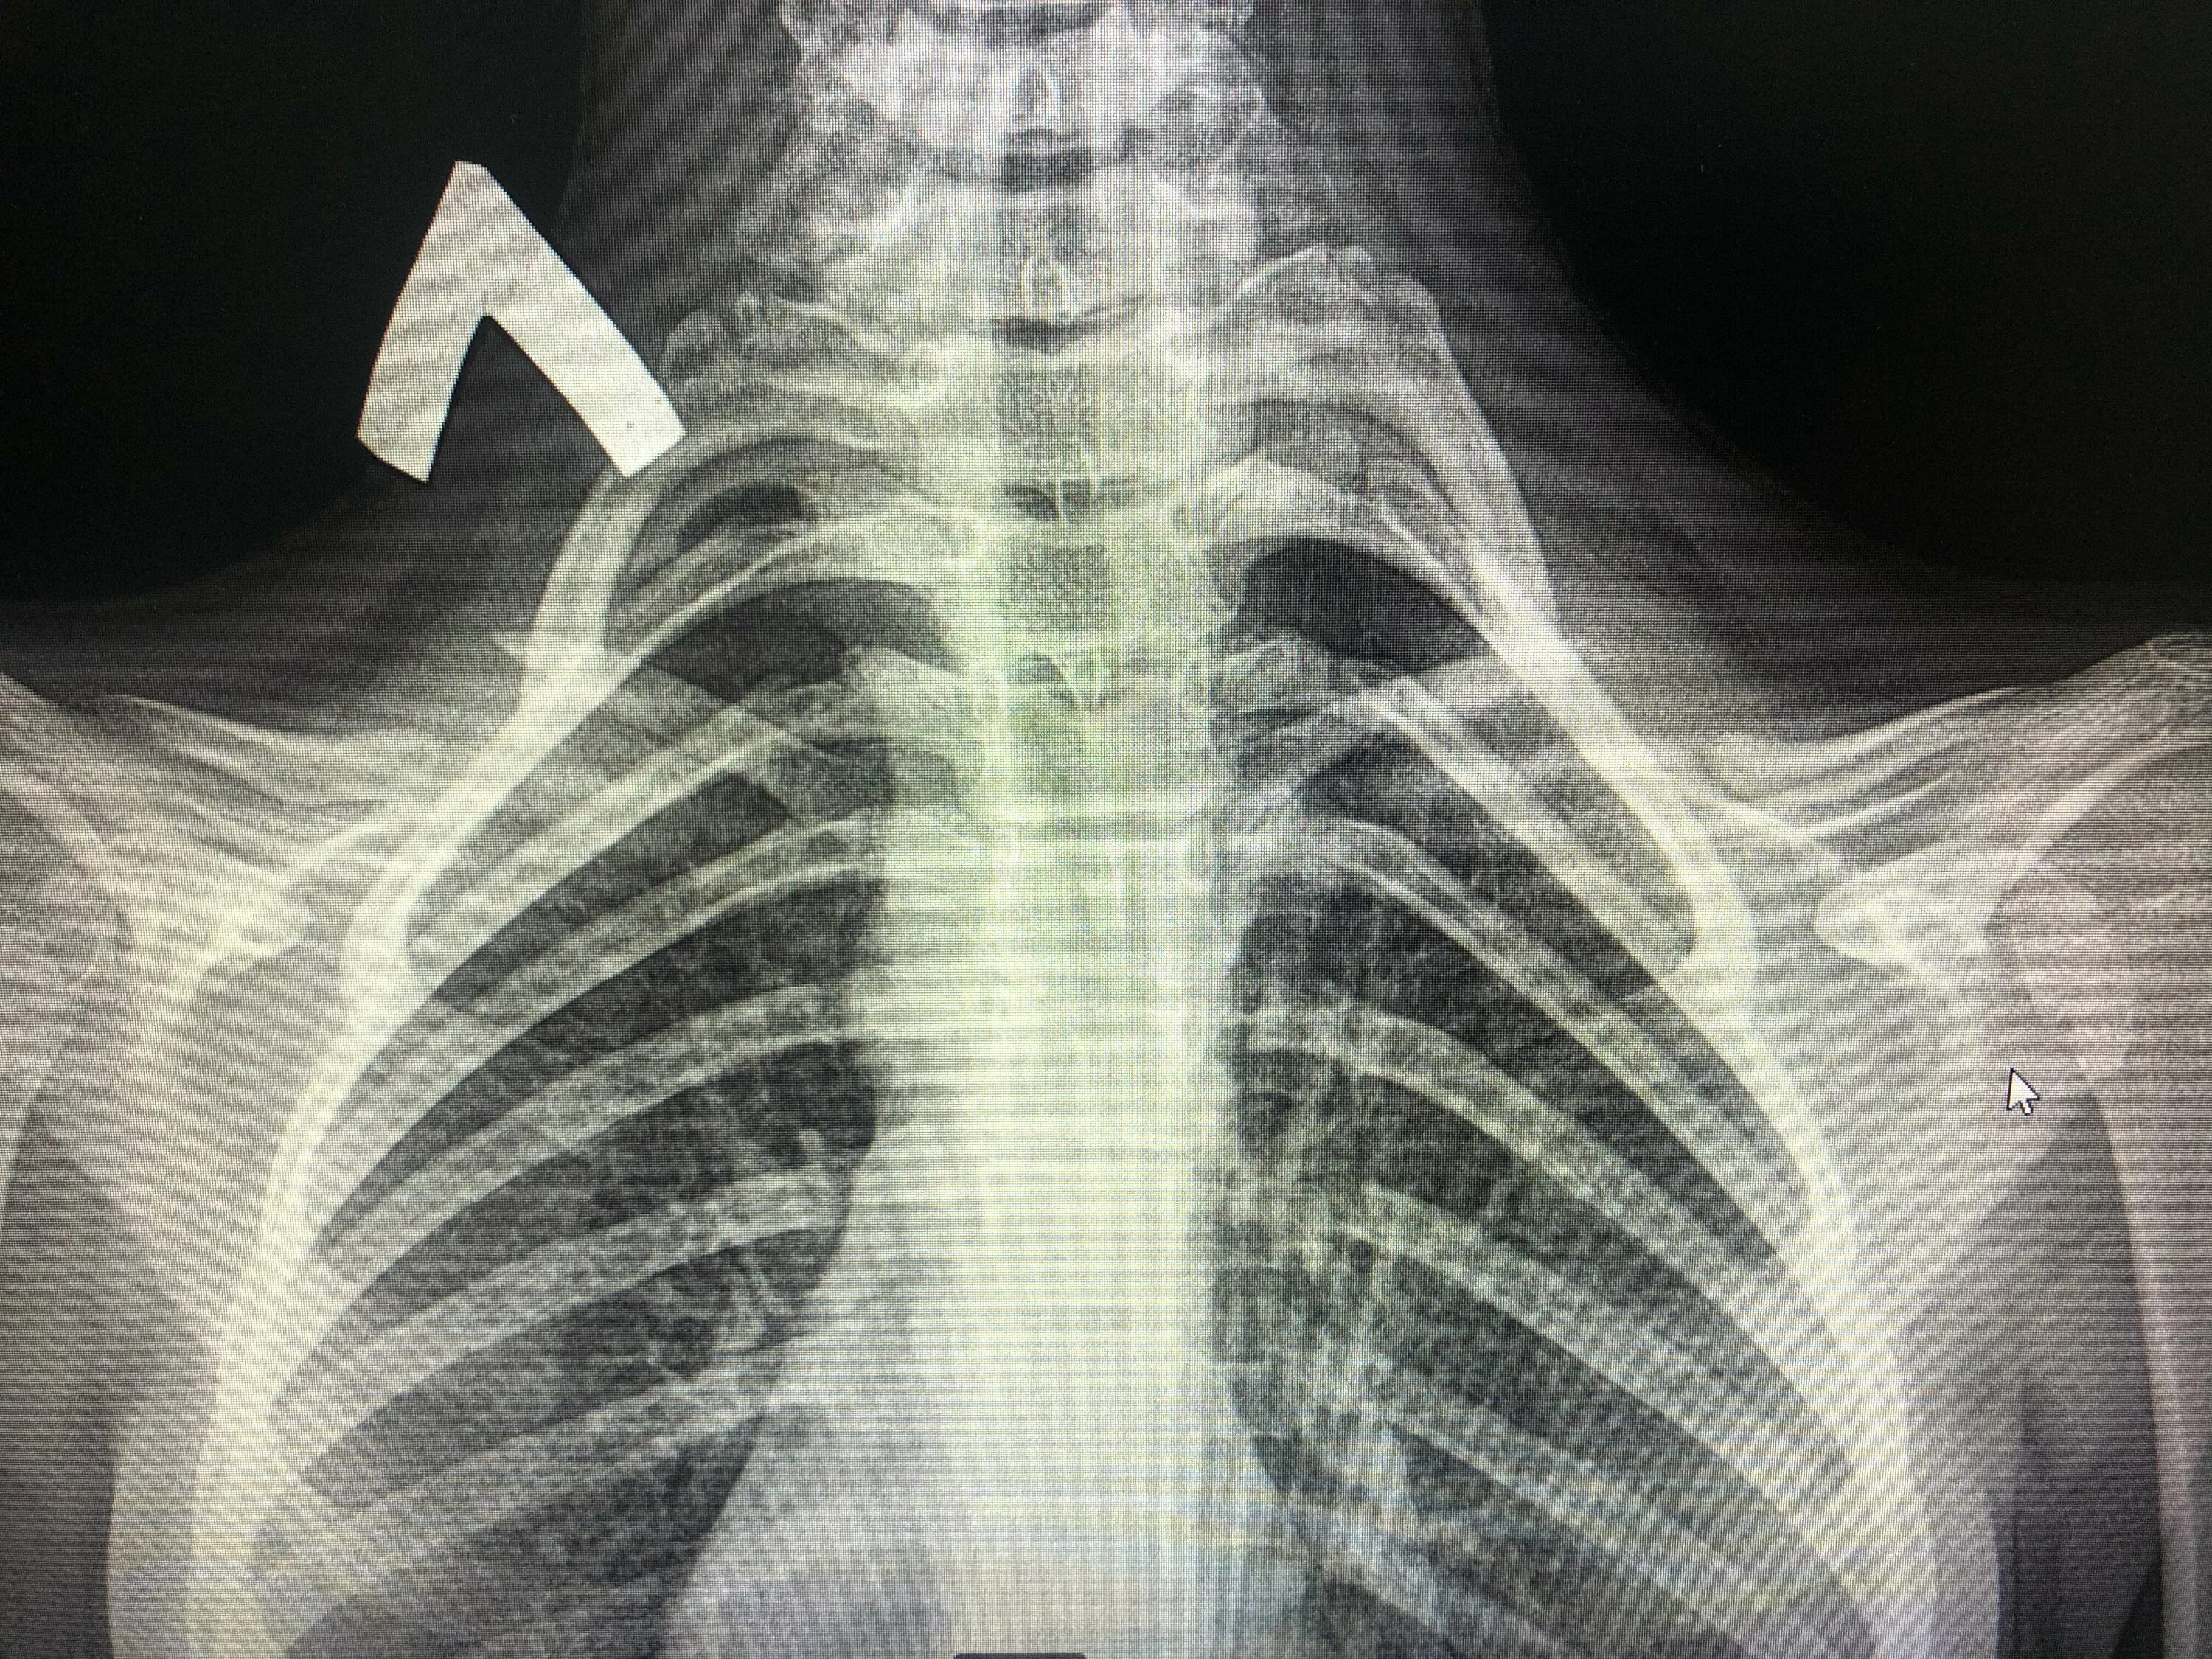

Гипоплазия 12 пары ребер